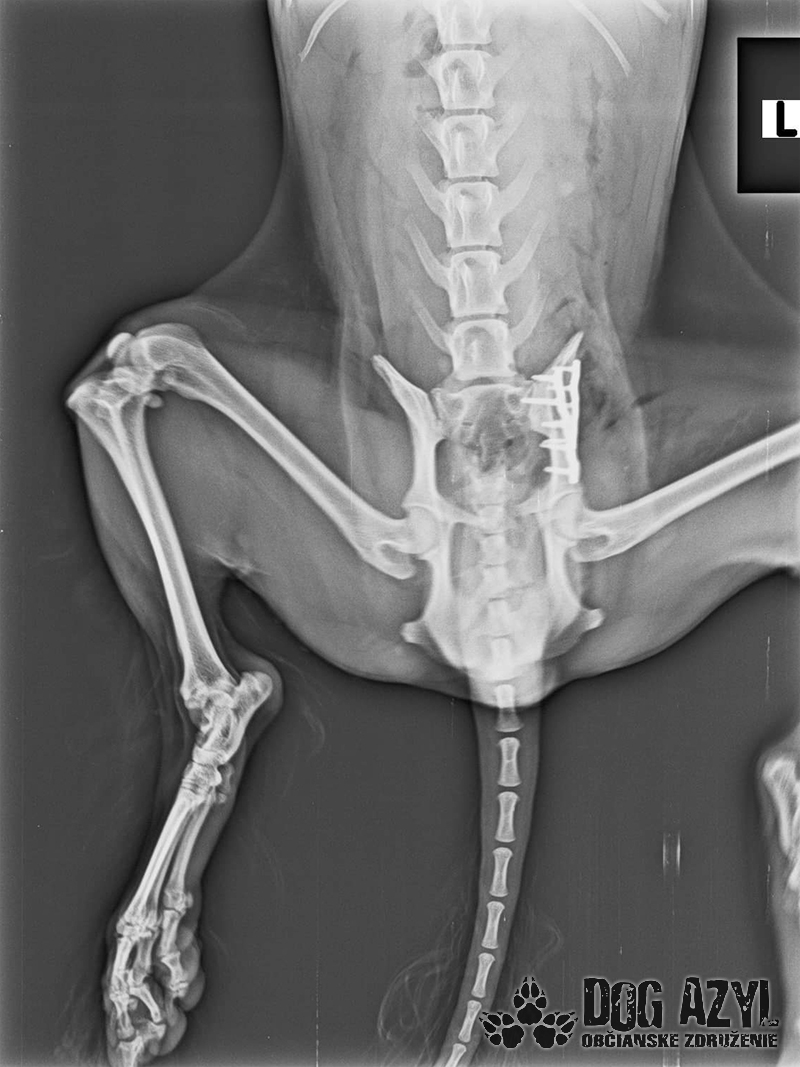

Bola neskutočne zanedbaná, hladná a dolámaná. Panvu má zlomenú na troch miestach, od úderu jej praskol močový mechúr a mala na sebe snáď všetky blchy sveta, žrali ju zaživa. Zotavuje sa.. Pomaličky, ale zotavuje sa po náročných operáciách a dúfame, že bude opäť v poriadku. Bude potrebovať rehabilitovať, aby vedela opäť behať, ale zabezpečíme jej úplne všetko, čo bude treba!!

A teraz si kladiete otázku, že prečo my a nie pôvodná rodina, že? Lebo sme tu pre to aby sme pomohli psíkom, ktorí majiteľa nemajú, alebo ich majitelia nemajú možnosť pomôcť im. Rodina sa s Miou musela rozlúčiť pred rokom z vážnych dôvodov, ktoré samozrejme rozoberať nebudeme. Mia má teraz nás a samozrejme Vás. Je to skromné, pokorné a neskutočne prítulné stvorenie, ktoré so sebou i napriek bolestiam nechá robiť čokoľvek lebo vie, že sa to robí v jej záujme. Mimi (ako ju volám) bude mať 17.5.2021 šieste narodeniny a dala som jej sľub, že poprosím dobrých ľudí, aby sme oslavovali spolu jej nový začiatok. Prijali sme ju pod naše združenie s vierou, že keď sa spojíme pre jej dobro, zvládneme náklady na operácie a rehabilitácie. Pomôžete nám prosím? Sú to opäť nečakané náklady, na ktoré sme neboli pripravené, úspory žiaľ už nemáme žiadne a príjem z 2% je ešte v nedohľadne. Prikladáme aj Miuškinu faktúru za ortopedickú operáciu, rekonštrukciu panvy. Faktúru za operáciu prasknutého mechúra ešte nemáme, a s rehabilitáciou ešte iba začneme. Pomôže nám ozaj každé euro.